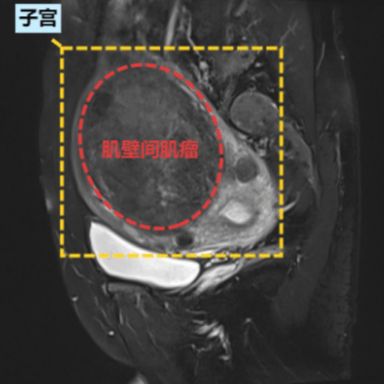

肌壁间肌瘤完全埋藏在“墙壁”内部。只要它不大,通常很“安静”,可能没有任何感觉。但如果它长大了,就会让“墙壁”变厚、子宫增大,也会挤占宫腔。

根据肌瘤生长部位,可以分为子宫体肌瘤(约占90%)和子宫颈肌瘤(约占10%)。根据和子宫壁的关系,也可分为肌壁间肌瘤、黏膜下肌瘤、浆膜下肌瘤及阔韧带肌瘤。不同类型的肌瘤对妊娠的影响各异。

●Ⅳ型:完全位于肌壁间(远离内膜和浆膜层)

如果是肌壁间肌瘤,可能部分会影响宫腔形态,根据患者的症状、肌瘤的大小和部位,部分患者可能需要行子宫肌瘤剥除术。